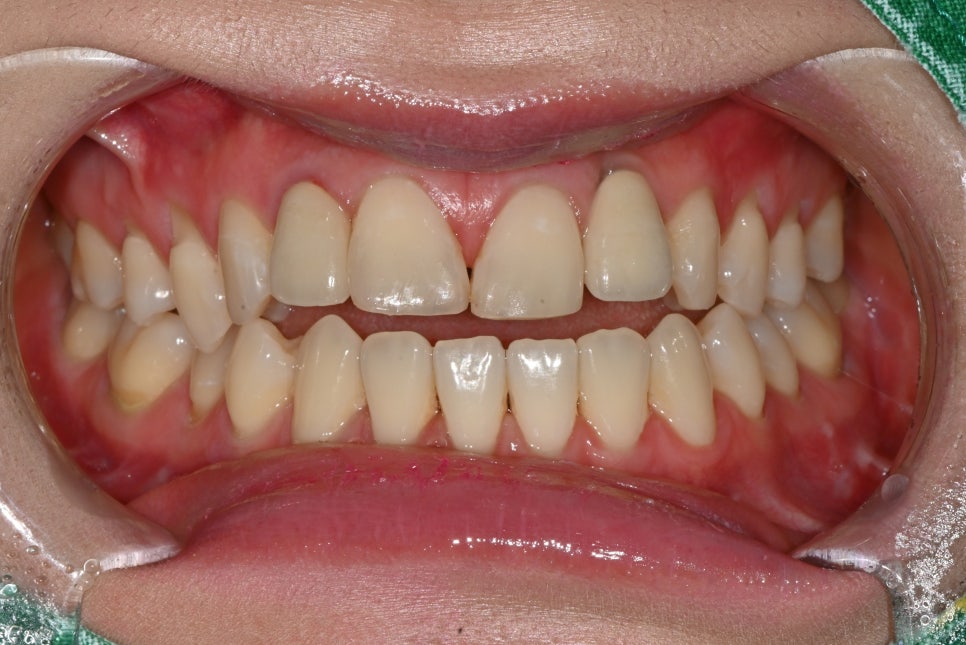

라미네이트, 임플란트 시술 전

앞니는 웃을 때 가장 먼저 보이는 부위인 만큼 작은 차이도 전체 인상에 크게 영향을 줍니다.

특히 기존 임플란트의 색감이나 모양, 위치감 때문에 어색해 보이는 경우에는 환자분들이 라미네이트를 고려하시는데, 라미네이트는 자연치아에만 시술할 수 있기 때문에 일부는 임플란트, 일부는 라미네이트로 시술해야 합니다.

내원 전 고민

환자분은 기존 앞니 임플란트가 주변 자연치와 잘 어우러지지 않아 웃을 때마다 어색한 느낌이 신경 쓰인다고 하셨습니다.

특히 임플란트는 식립해놓은 보철물이 내려가거나 잇몸과의 경계가 깔끔하게 들어맞지 않으면 티가 굉장히 많이 납니다.

기존 임플란트